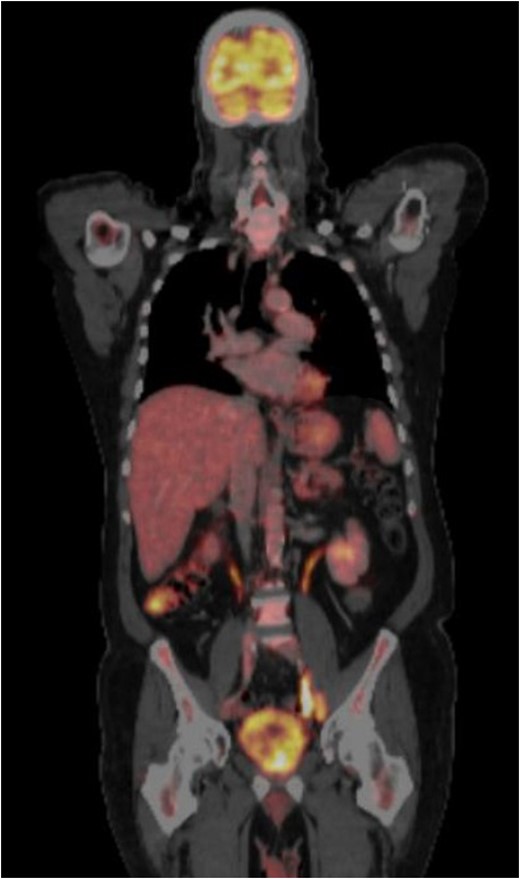

CT-PET performed after surgery showing metastatic disease with local recurrence of the mass extending into the cystectomy bed.